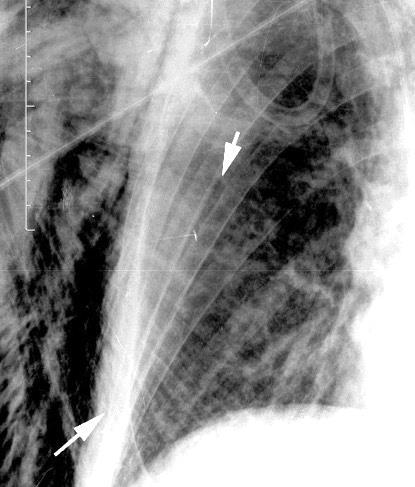

Carcinoma de mama izquierda

Nódulo en língula.

Cirugía de Ca .de mama hace 23 añosedema de brazo y ganglio en axila. ¡Metástasis!.

Ecanow JS et l. Axillary Staging of Breast Cancer: What the Radiologist Should Know. Radiographics 2013